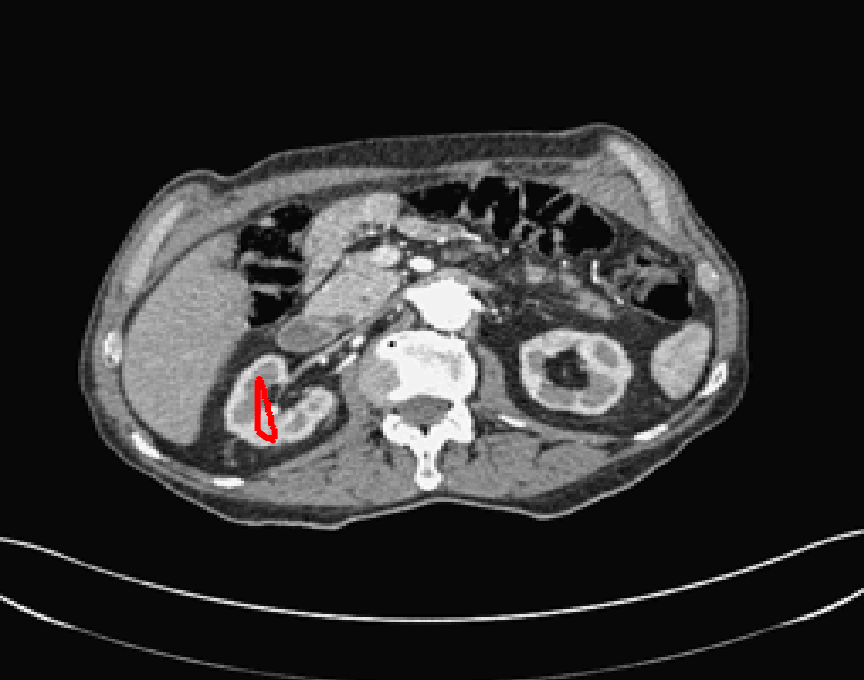

The motivation for this work comes from observing contradictions in using piecewise-constant intensity fitting terms in selective segmentation. Whilst good results are possible with this approach, the exceptional cases lead to severe limitations in practice. This is quite common in medical imaging as demonstrated in Fig. 1, where the target foreground has a low intensity. Given that the corresponding background includes large regions of low intensity, the optimal average intensities for this segmentation problem are and . For cases where , we see that by (1), almost everywhere in the domain . This means that it is very difficult to achieve an adequate result, without an over-reliance on the user input or parameter selection.

| (10) |

where is noise, is the characteristic function of the region , for respectively. The idea of selective segmentation is to incorporate user input to apply constraints that exclude regions classified as foreground, based on their location in the image. We use a distance constraint which penalises the distance from the user input markers. However, a key problem for selective segmentation is that for cases where the optimal intensity values and are similar, the intensity fitting term will become obsolete as the contour evolves. This is illustrated in Fig. 3. The purpose of our approach is to construct a model that is based on assumptions that are consistent with the observed image and any homogeneous target region of interest. A common approach in selective segmentation is to discriminate between objects of a similar intensity Rada:13 ; Geo ; CDSS . However, the fitting terms in previous formulations Klodt:13 ; Rada:13 ; Geo ; CDSS aren’t applicable in many cases as there are contradictions in the formulation in this context. We will address this in detail in the following section.

for and as defined in (33). This is consistent with respect to the intensities of the observed object and the concept of selective segmentation. In Fig. 3 we see the difference between CV and the proposed fitting terms for given user input on a CT image. For the CT image, the CV fitting terms are near 0 within the target region. This is despite there being a distinct homogeneous area with good contrast on the boundary. This illustrates the problem we are aiming to overcome. With the proposed fitting term this phenomenon should be avoided in cases like this. By defining as in (33) there is no contradiction if the foreground and background intensities of the target region are similar.